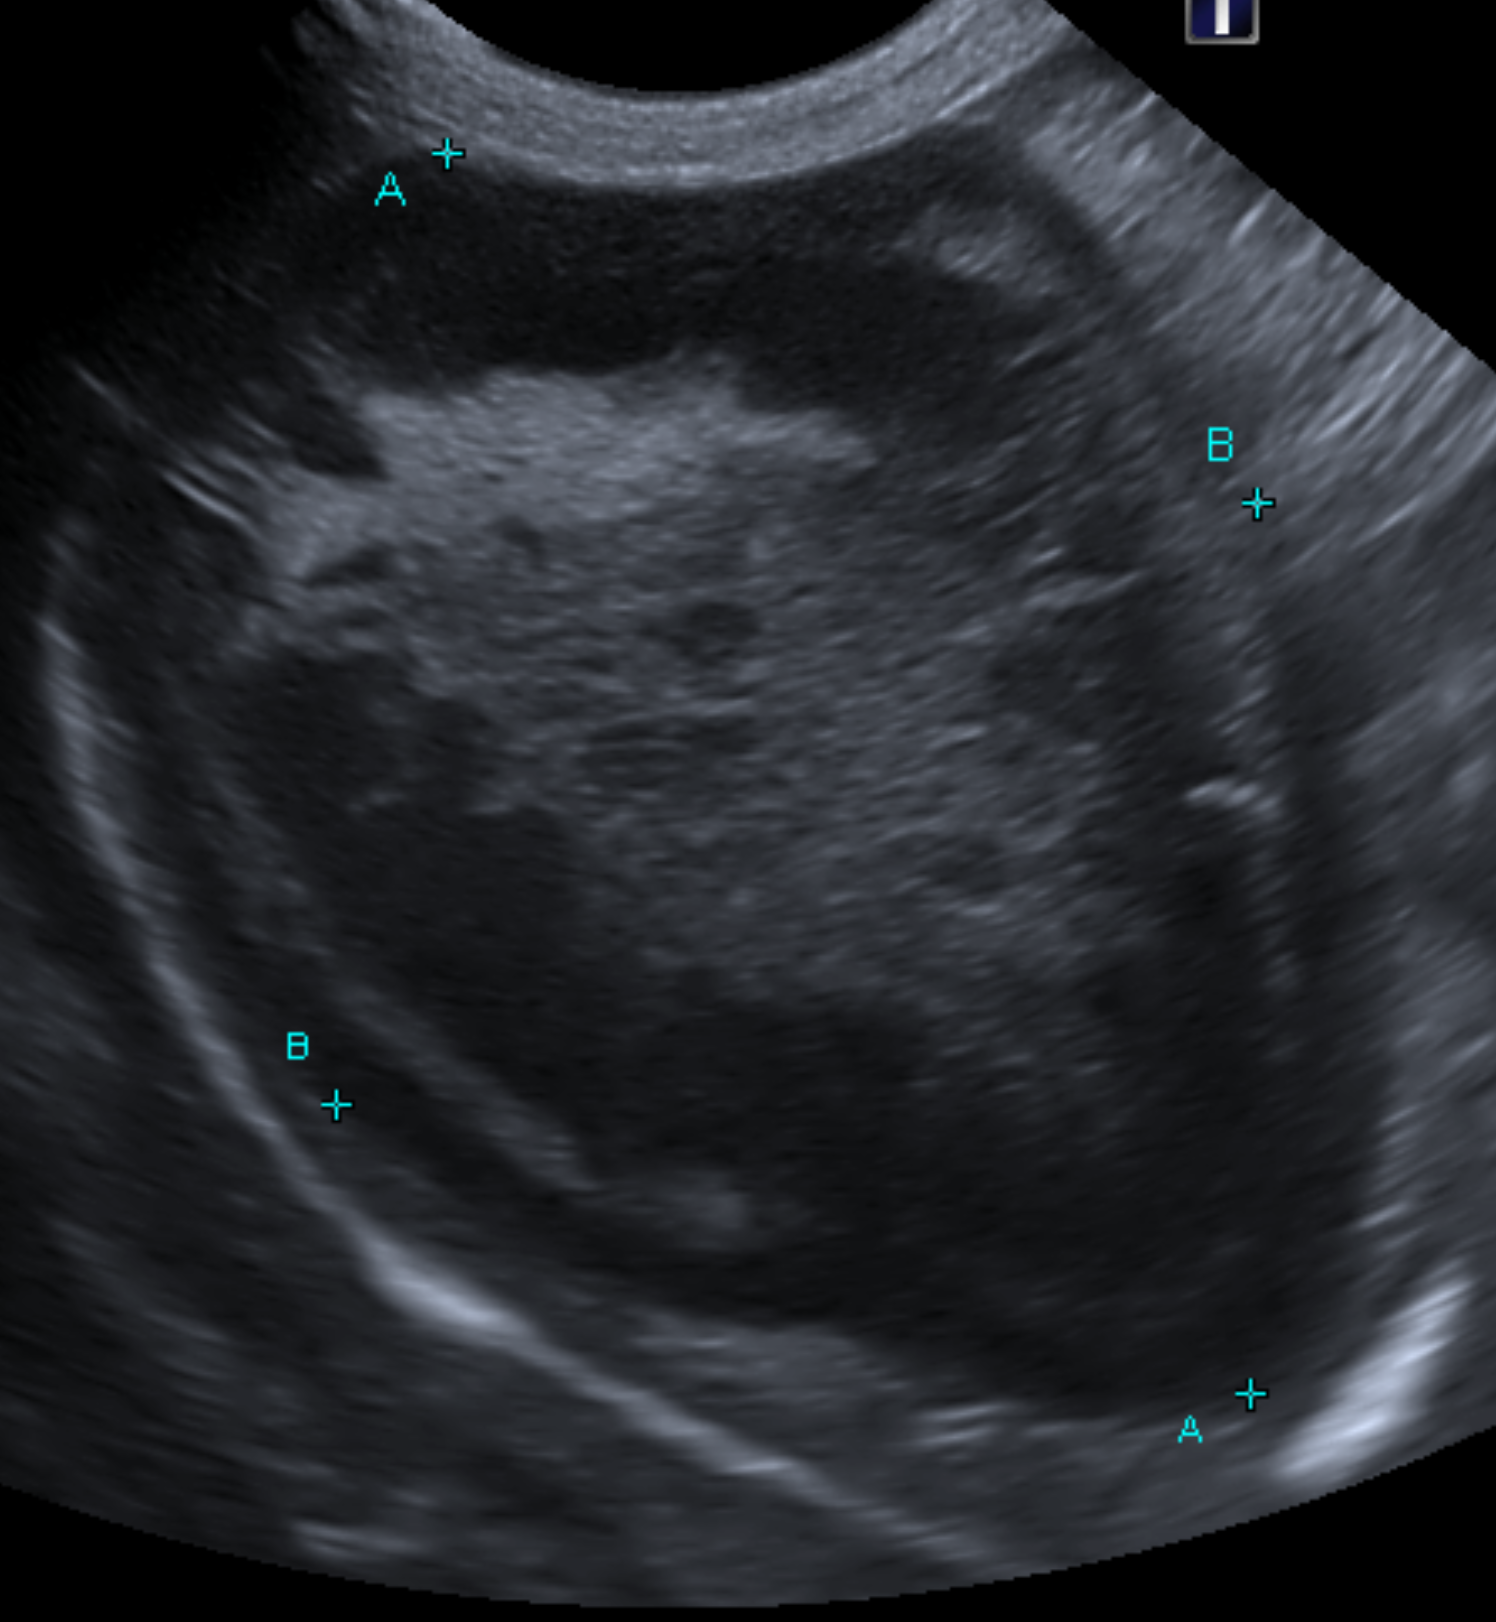

血液検査においては肝数値の上昇、T-Bilの上昇、超音波画像検査においてはキウイフルーツの様な特徴的な胆嚢の内腔の見え方を示します。

超音波画像を示します。

こちらが典型的なキウイフルーツ様を示す胆嚢です。